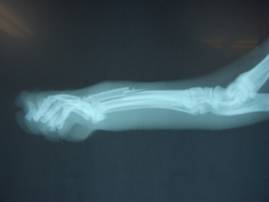

今回は相談の上、ギブス固定を行うことになりました。

ギブスを巻いた様子。上からオレンジの包帯で保護してあります。